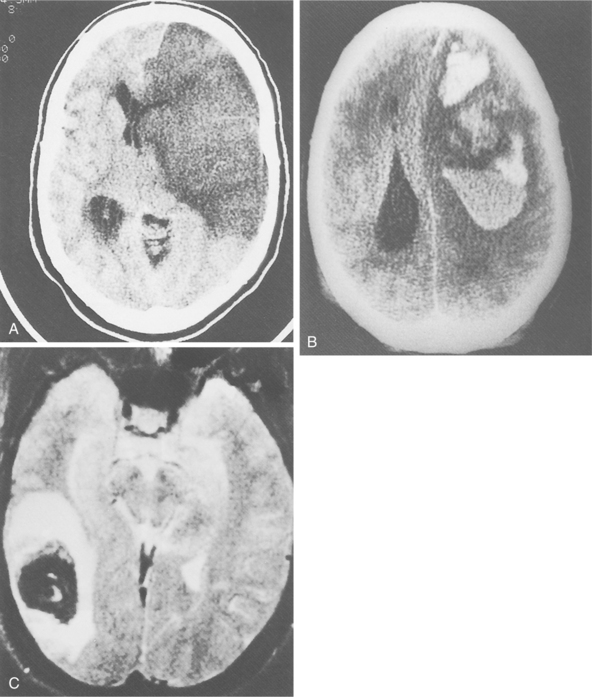

Cerebrovascular disease, the primary cause of stroke, is caused by one of several pathologic processes involving the blood vessels of the brain. The damage may be intrinsic to the vessel, or the stroke may originate remotely, such as when an embolus from the heart or extracranial circulation lodges in an intracranial vessel. The stroke may result from the rupture of a vessel in the subarachnoid space or intracerebral tissue. Fig. 32-1 shows the effects of different types of stroke on brain tissue.98

Figure 32-1 Radiographic images of the brain after stroke. A, An acute infarct with mass effect and compression of the ventricle. B, An acute intracerebral hemorrhage in the hemisphere. C, Amyloid angiopathy with acute hemorrhage; the edema surrounding the area results in a slight mass effect on the midbrain. (Reprinted from Ramsey R: Neuroradiology, Philadelphia, 1994, WB Saunders.)